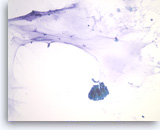

Benign gastric epithelial cells,

Pancreas FNA, Direct Smear.

Normal gastric epithelial cells form a large cohesive sheet. The epithelial cells are small and uniform, arranged in an orderly fashion. Gastric contaminants can be seen during trans-gastric FNA of pancreatic lesions. It can be difficult or impossible to distinguish gastric mucosal cells from either benign biliary epithelium or low-grade mucinous cystic neoplastic epithelium on direct smears.

10X

Benign gastric epithelial cells,

Pancreas FNA, Direct Smear.

Normal gastric epithelial cells form a large cohesive sheet. The epithelial cells are small and uniform, arranged in an orderly fashion. Gastric contaminants can be seen during trans-gastric FNA of pancreatic lesions. It can be difficult or impossible to distinguish gastric mucosal cells from either benign biliary epithelium or low-grade mucinous cystic neoplastic epithelium on direct smears.

10X